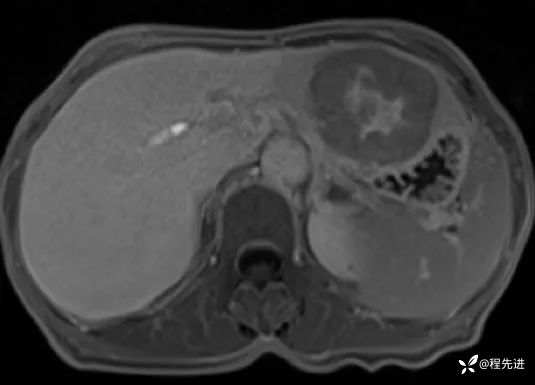

简要病史:超声体检发现肝占位8天,否认腹痛等不适

实验室检查:CA125 39.4 U/mL,NSE 24 ng/mL,Cyfra211 5.6 ng/mL,HBsAg、anti-HCV、AFP、CEA、CA19-9均(-)

CT平扫:

T2压脂: